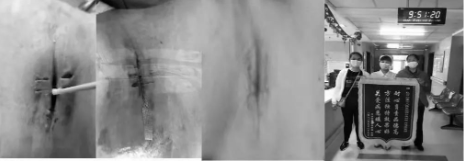

例如,患者黄某某,胸部手术后切口感染2月余未愈合,经历3次二期缝合,伤口仍然未愈合,于2022年2月14日到伤口门诊就诊,患者诉说:“伤口愈合不了带来的苦恼,超过了手术成功的喜悦,我已经快抑郁了”。护士姐妹们看在眼里,痛在心里。采取湿性新型敷料促进自容清创+透明薄膜间断拉合技术+免缝针治疗切口感染,3月16日,患者伤口完全愈合,专门送来感谢的锦旗。